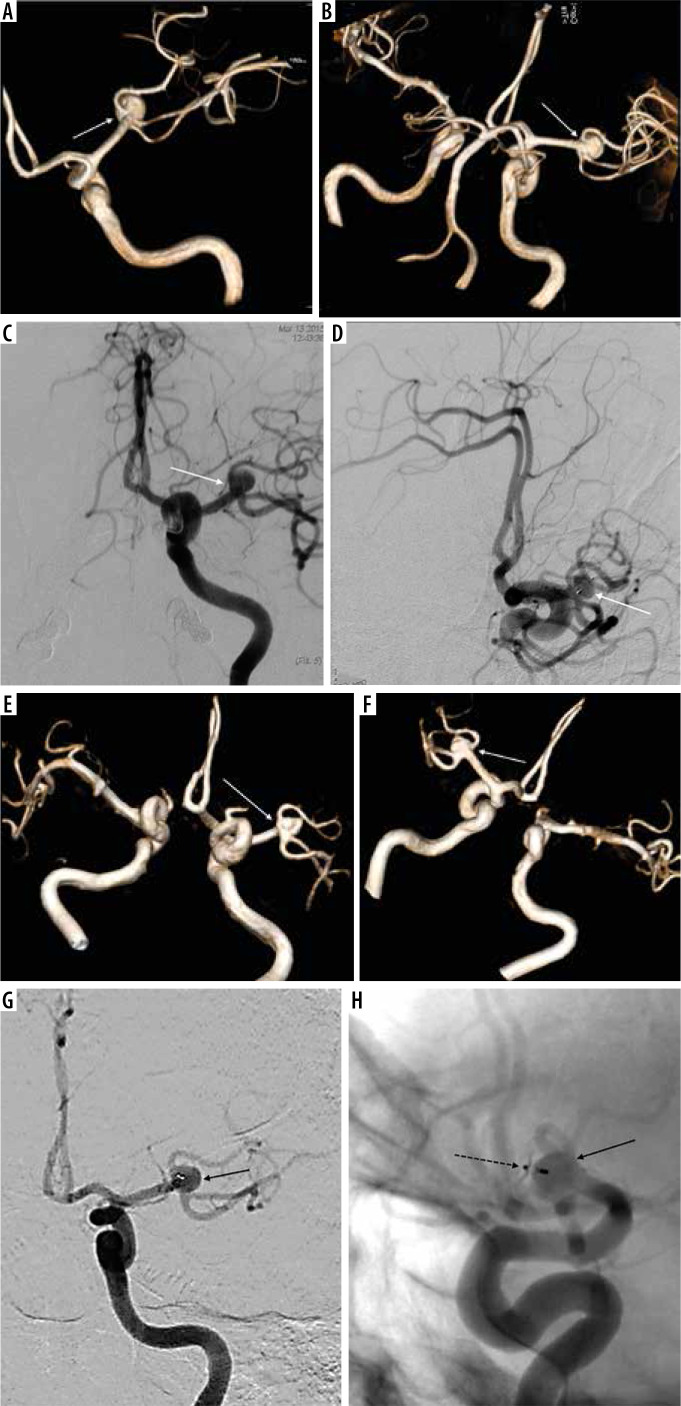

Case presentation: We presented a longitudinal case report with several 3D-TOF MRA prints over time. Three-tesla 3D-TOF data were converted into STL and G-code files using an open-source (3D-Slicer) program. We built patient-specific realistic 3D models of a patient with a middle cerebral artery trifurcation aneurysm, which were able to demonstrate the entire WEB device treatment procedure in the pre-intervention and post-intervention periods. The aneurysmatic segment was well displayed on the STL files and the 3D replicas. They allowed visualization of the aneurysmatic segment and changes within a 6-year follow-up period. We successfully showed the possibility of fast, cheap, and easy production of replicas for demonstration of the aneurysm, the parent vessels, and post-intervention changes in a simple way using an affordable 3D printer.